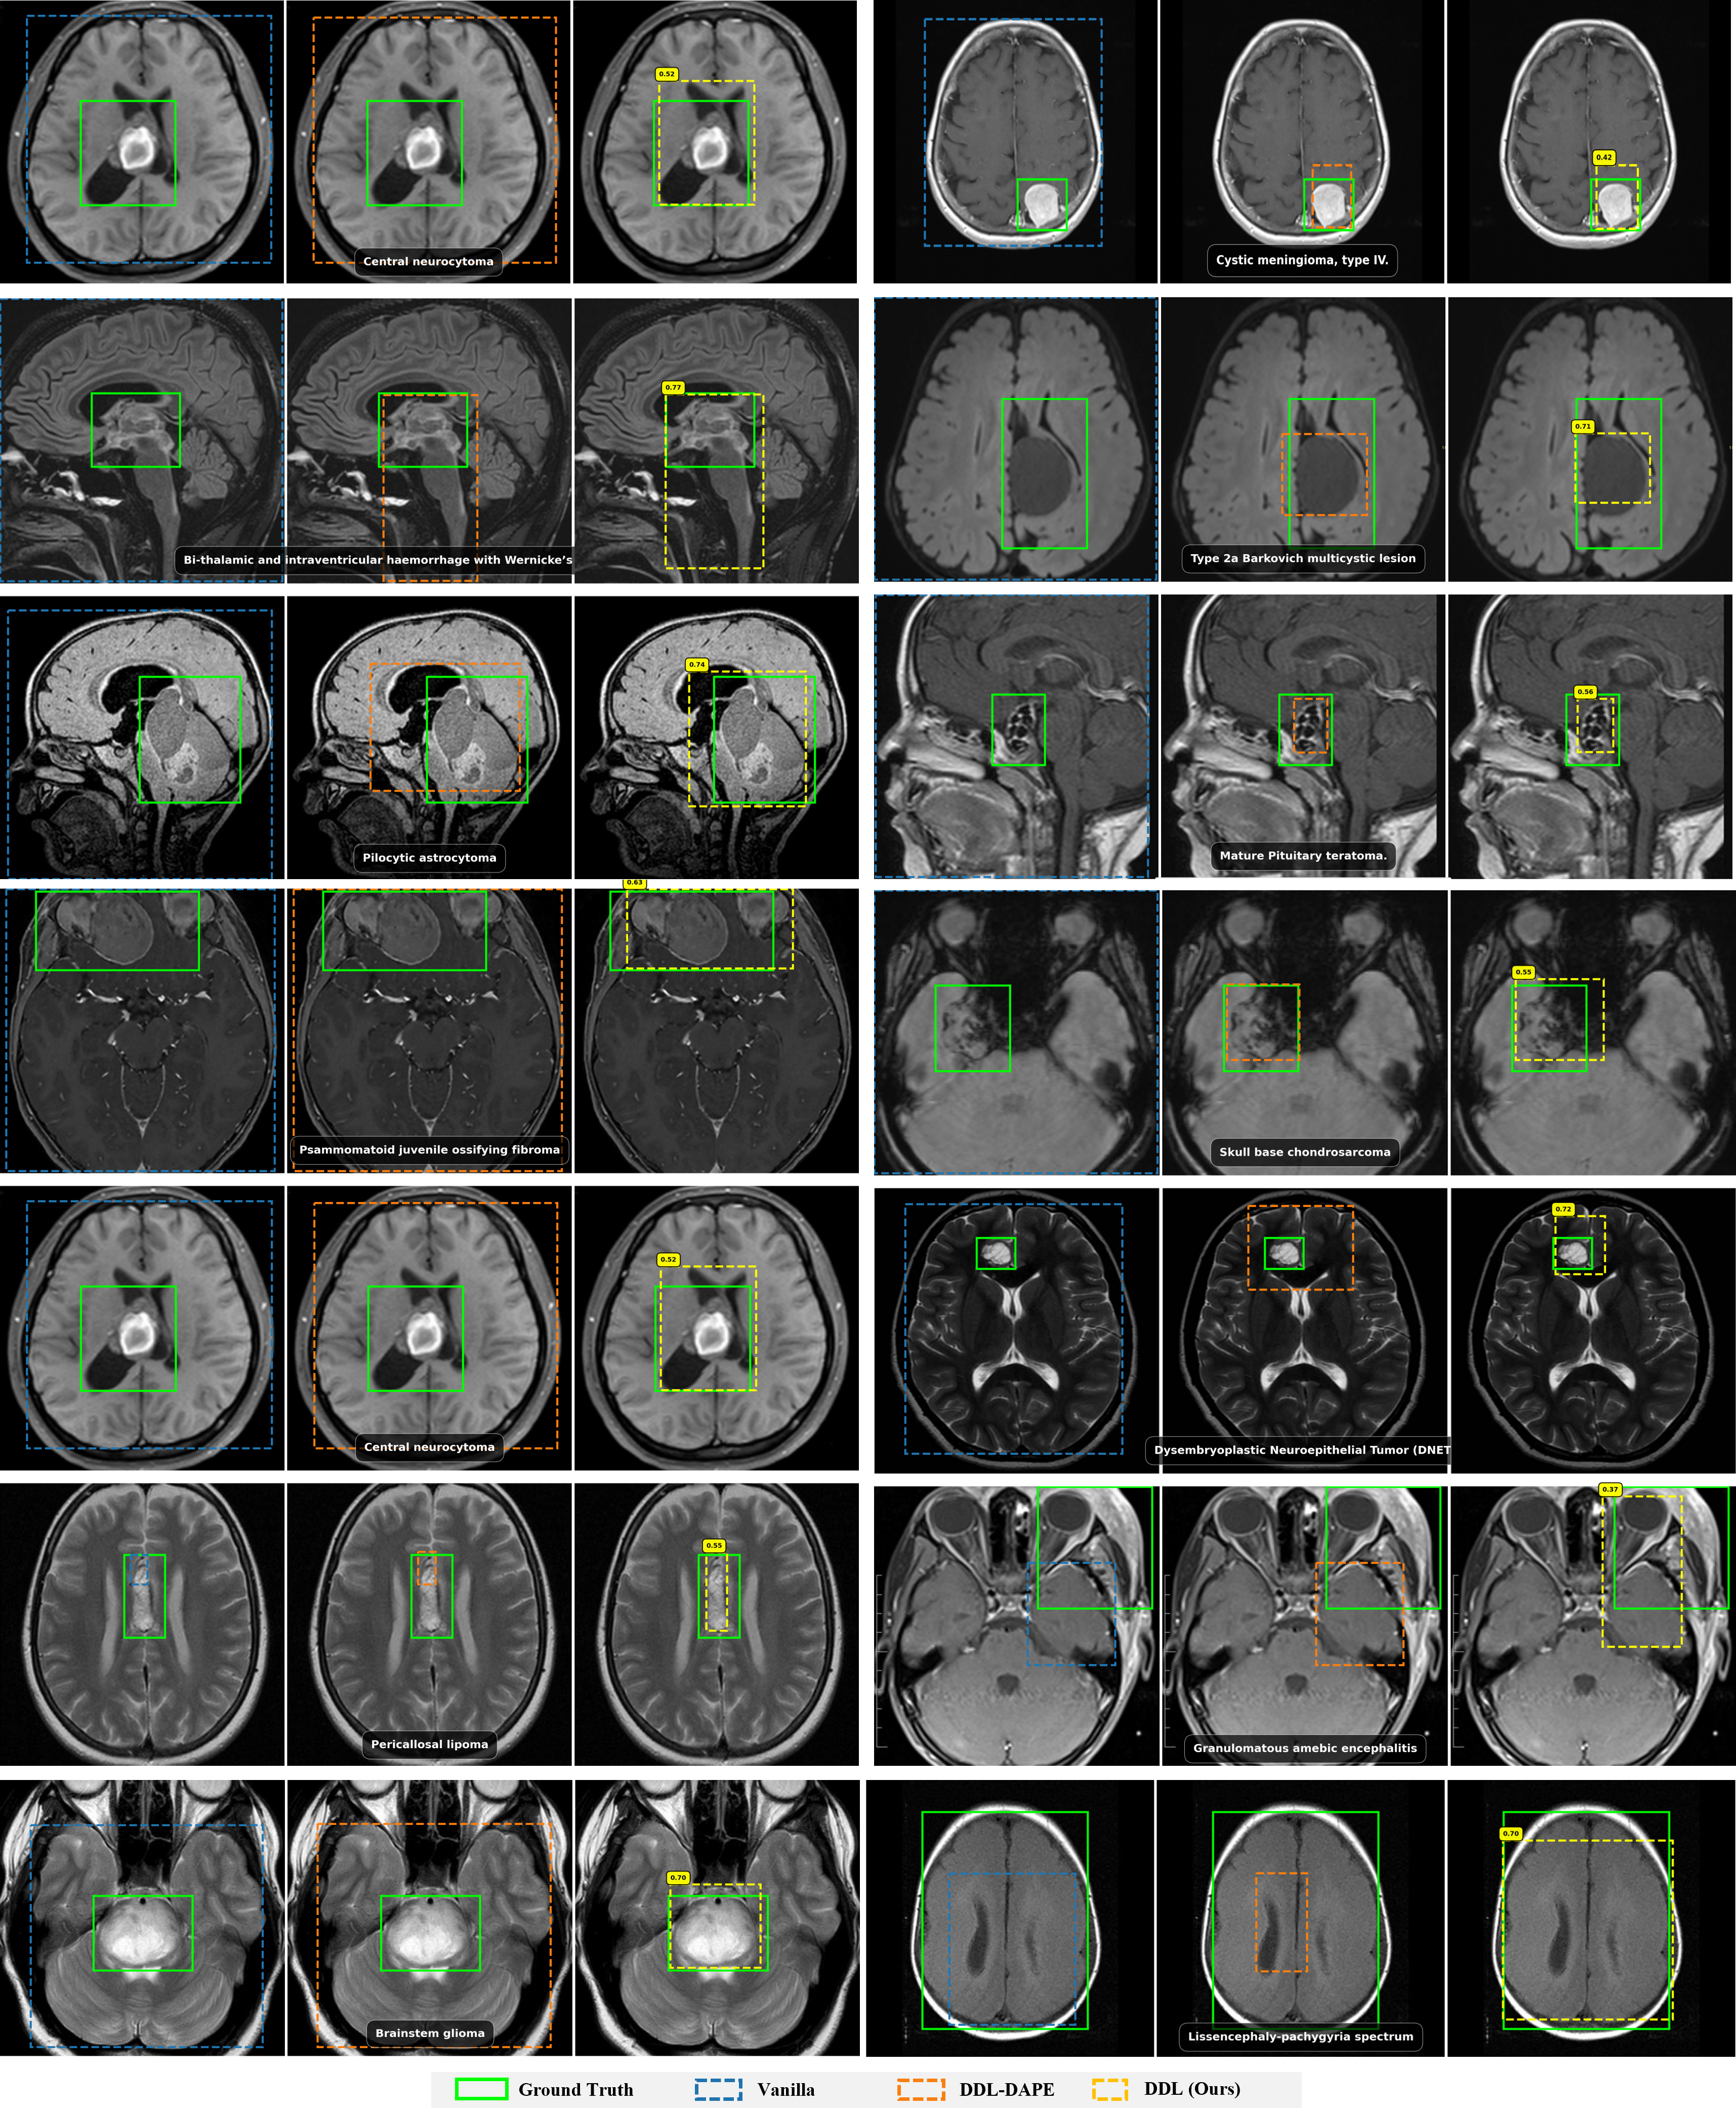

32B Results

Qwen2.5-VL-32B Grounding Performance